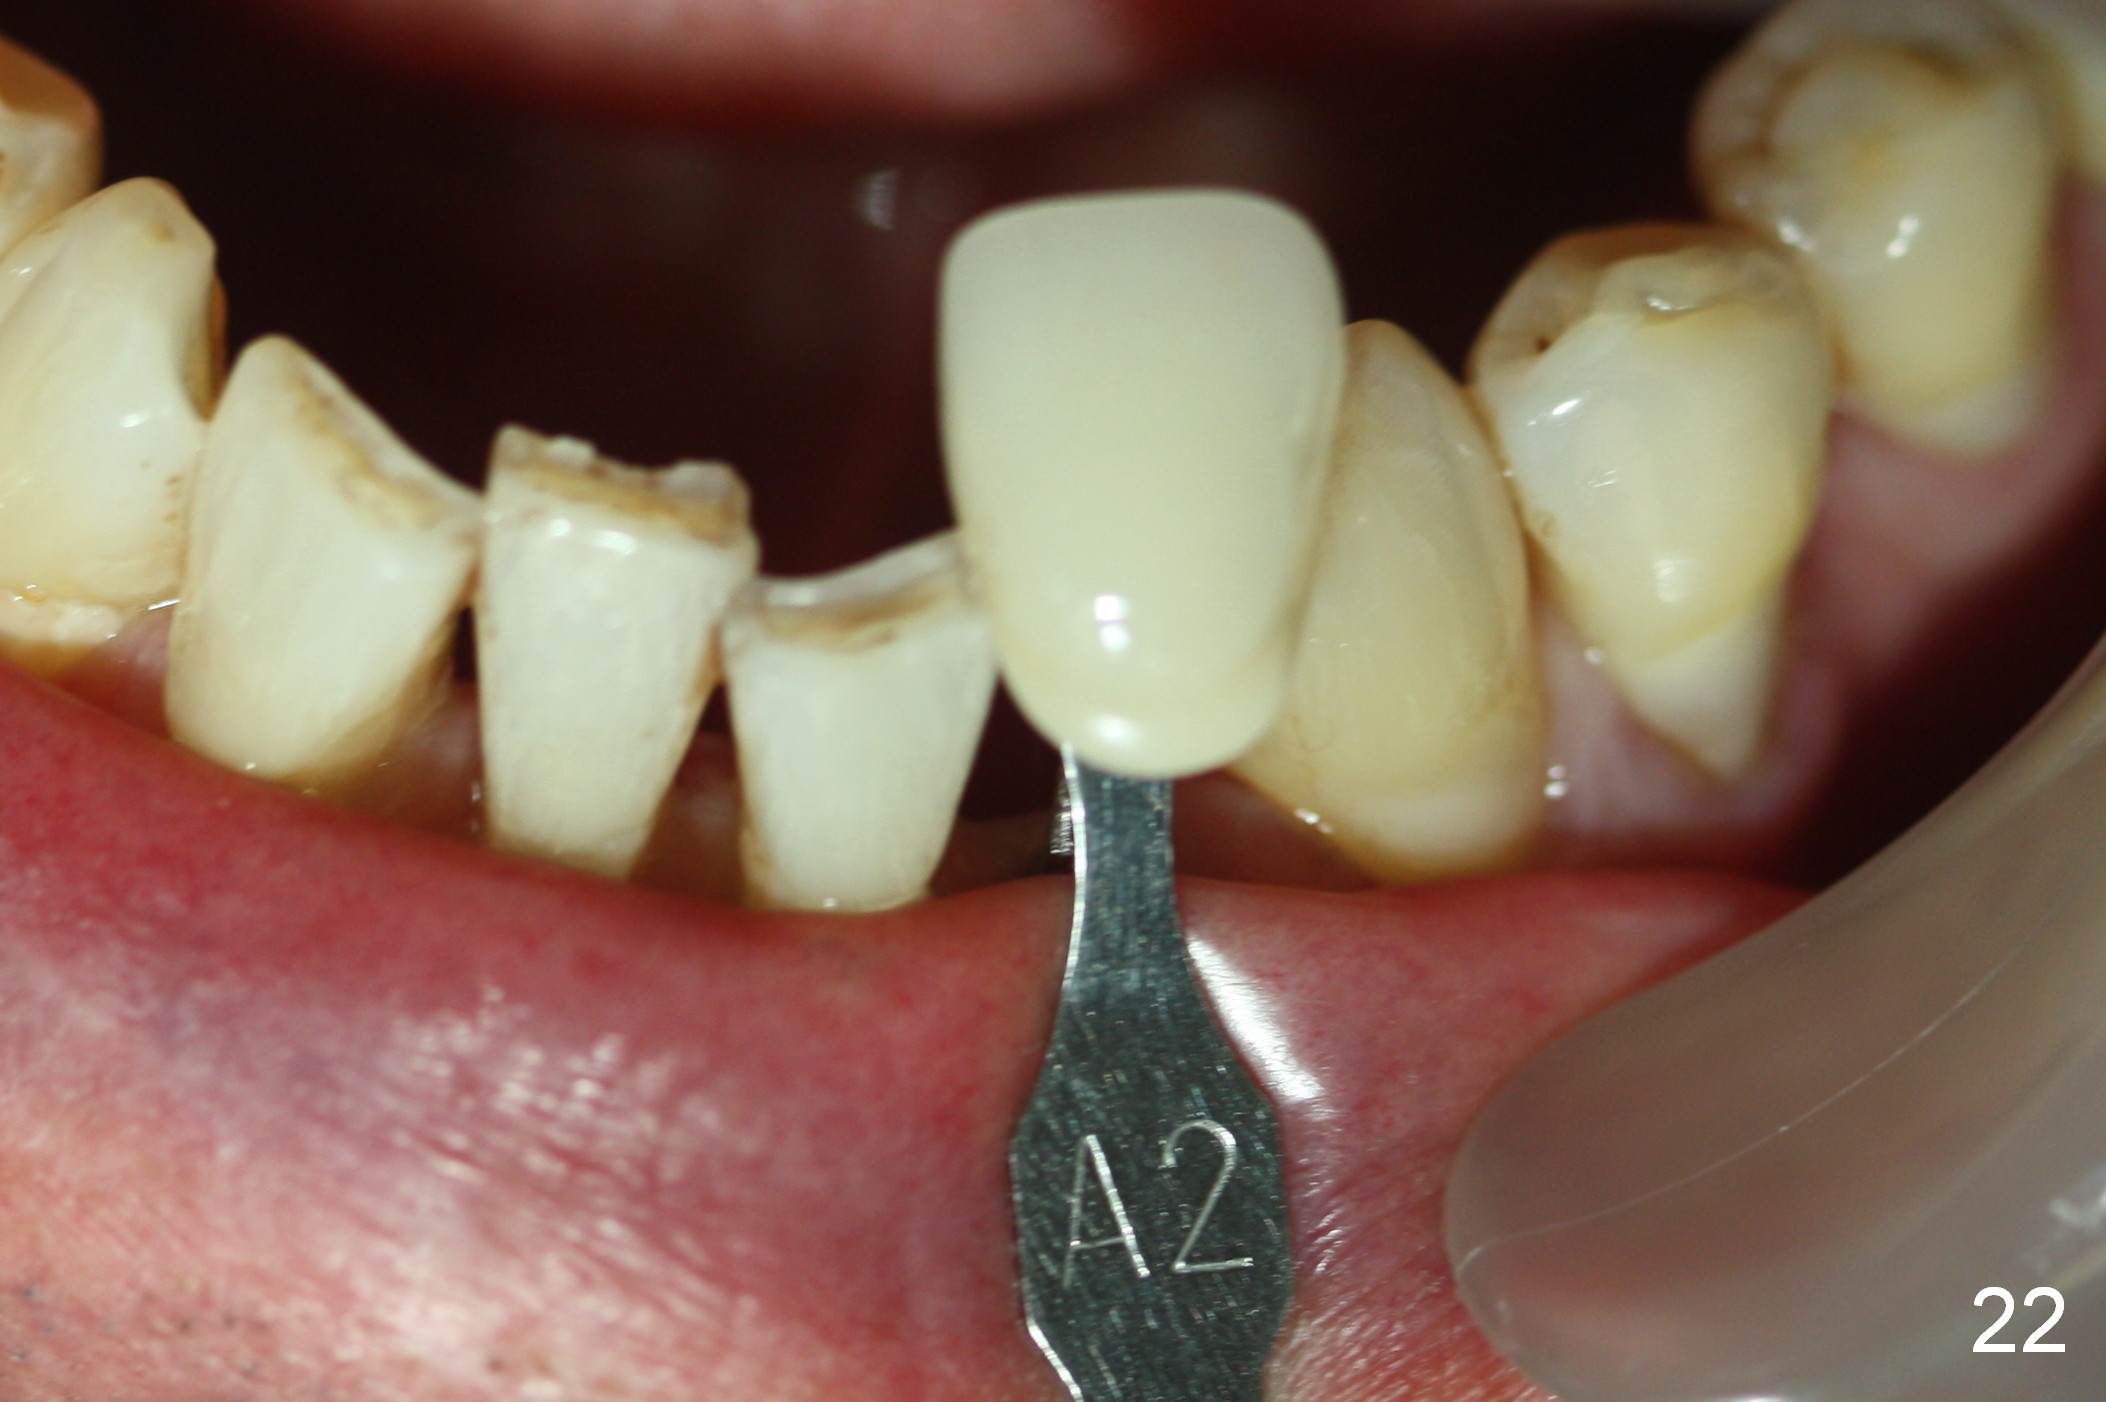

A 74-year-old man has several missing teeth (Fig.1).  His 1st goal is to replace the lower left lateral incisor (Fig.2).  The residual root has an apical lesion (Fig.3 *).  To describe intraop findings, a CT image of a different patient is used (Fig.4 coronal section; B: buccal; L: lingual).  After extraction, the buccal plate is found to be thin and low (Fig.5 arrowheads).  A 1.5 mm pilot drill (Fig.6 red line) is used to initiate osteotomy in the lingual plate of the socket.  Once the drill penetrates the lingual plate, the trajectory changes and the depth is 17 mm from the gingival margin (Fig.7).  A PA is taken (Fig.8); it appears that the osteotomy can be extended more apically.  When the pilot drill extends to 20 mm, there is sudden empty feeling.  The lingual plate has perforated (Fig.9).  A new osteotomy is established buccally (Fig.10 pink).  To avoid buccal plate perforation, especially in the buccal undercut area (>), the coronal end of the drill has to be tilted buccally (<--).  An angled abutment (3x20 mm, 15°) is placed (Fig.11,12).  The abutment is modified (Fig.13,14) to accommodate an immediate provisional (Fig.15,16 P).  Perio dressing is to be applied to prevent the bone graft from getting dislodged buccally (Fig.15).  The dressing is in place 7 days postop (Fig.17).

Five months postop, the peri-implant space reduces (Fig.18).  A keratinized band forms buccal to the implant (Fig.19 *).  The provisional dislodges probably due to the buccal placement (Fig.20).